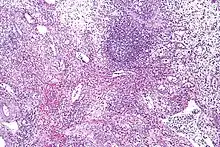

Eosinophilic cystitis showing edematous and chronically inflamed lamina propria with numerous eosinophils. | |

Cystoscopy typically reveals large mucosal edema along with erythematous, polypoid, velvety red lesions. It can be mistaken for vesical rhabdomyosarcoma in children.[25] Eosinophilic cystitis is hard to differentiate from other cystitis types (like interstitial and tuberculous cystitis), neoplastic lesions (like carcinoma in situ), and other bladder cancers. Therefore, in order to confirm the diagnosis of eosinophilic cystitis, biopsies are required.[2] Transmural inflammation is present histologically, primarily with eosinophils. The lamina propria has more severe edema and inflammation. A contracted bladder may result from focal muscle necrosis and varying degrees of detrusor muscle fibrosis.[26]